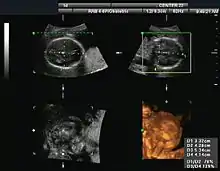

Gynecology and obstetrics

Gynecologic ultrasonography examines female pelvic organs (specifically the uterus, ovaries, and fallopian tubes) as well as the bladder, adnexa, and pouch of Douglas. It uses transducers designed for approaches through the lower abdominal wall, curvilinear and sector, and specialty transducers such as transvaginal ultrasound.[18]

Obstetrical sonography was originally developed in the late 1950s and 1960s by Sir Ian Donald[19][20] and is commonly used during pregnancy to check the development and presentation of the fetus. It can be used to identify many conditions that could be potentially harmful to the mother and/or baby possibly remaining undiagnosed or with delayed diagnosis in the absence of sonography. It is currently believed that the risk of delayed diagnosis is greater than the small risk, if any, associated with undergoing an ultrasound scan. However, its use for non-medical purposes such as fetal "keepsake" videos and photos is discouraged.[21]

Obstetric ultrasound is primarily used to:

- Date the pregnancy (gestational age)

- Confirm fetal viability

- Determine location of fetus, intrauterine vs ectopic

- Check the location of the placenta in relation to the cervix

- Check for the number of fetuses (multiple pregnancy)

- Check for major physical abnormalities.

- Assess fetal growth (for evidence of intrauterine growth restriction (IUGR))

- Check for fetal movement and heartbeat.

- Determine the sex of the baby